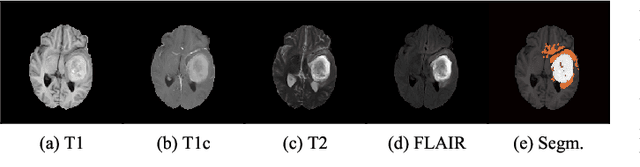

Abstract:Gliomas are the most common malignant brain tumors that are treated with chemoradiotherapy and surgery. Magnetic Resonance Imaging (MRI) is used by radiotherapists to manually segment brain lesions and to observe their development throughout the therapy. The manual image segmentation process is time-consuming and results tend to vary among different human raters. Therefore, there is a substantial demand for automatic image segmentation algorithms that produce a reliable and accurate segmentation of various brain tissue types. Recent advances in deep learning have led to convolutional neural network architectures that excel at various visual recognition tasks. They have been successfully applied to the medical context including medical image segmentation. In particular, fully convolutional networks (FCNs) such as the U-Net produce state-of-the-art results in the automatic segmentation of brain tumors. MRI brain scans are volumetric and exist in various co-registered modalities that serve as input channels for these FCN architectures. Training algorithms for brain tumor segmentation on this complex input requires large amounts of computational resources and is prone to overfitting. In this work, we construct FCNs with pretrained convolutional encoders. We show that we can stabilize the training process this way and produce more robust predictions. We evaluate our methods on publicly available data as well as on a privately acquired clinical dataset. We also show that the impact of pretraining is even higher for predictions on the clinical data.